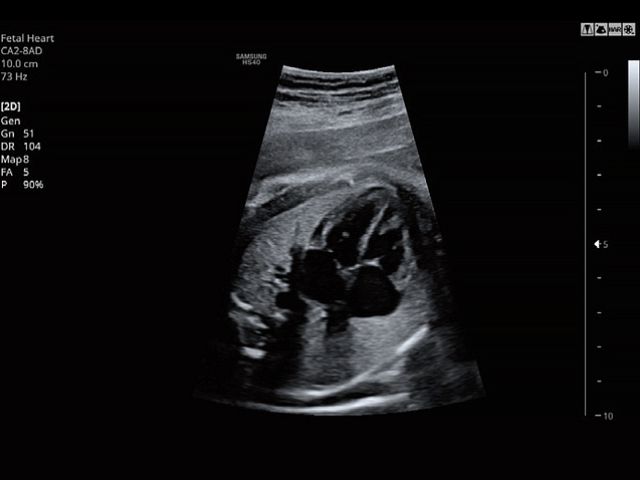

CA2-8ADApplication:Abdomen, Obstetrics, Gynecology, Pediatric, Musculoskeletal, Vascular, Urology, Emergency |